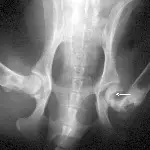

Figure 2A. The capital physis of this dog, which presented with hip pain, appears slightly widened.

Figure 2B. If the patient is positioned in a frog-legged position, the hairline fracture displaces and is easily diagnosed.